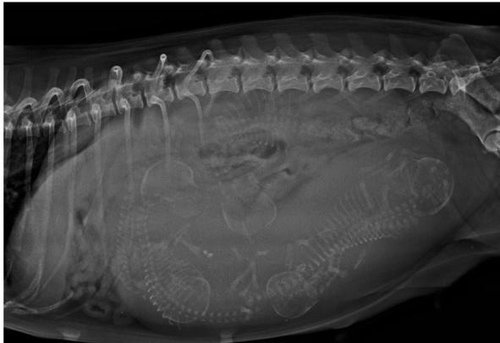

Olá, nossa cachorrinha vai precisar fazer uma cirurgia de cesária de emergência, são 5 filhotes e ela tem 8 anos, já gastamos muito com remédios, veterinários e etc, mais essa cirurgia está fora do nosso alcance agora é pra pouco prazo de pagar, obrigado a todos que conseguirem contribuir!!